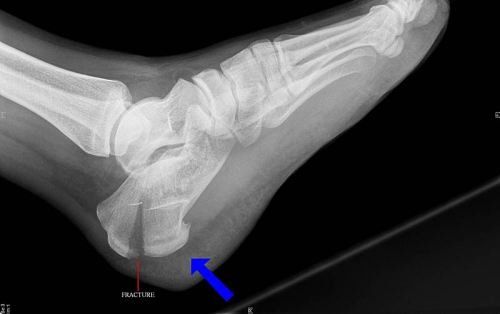

Переломы пяточной кости - это нарушение целостности пяточной кости вследствие травматического воздействия . Симптомы включают боли и отечность пяточной области, расширение и уплощение пятки . . .

Переломы пяточной кости . Пяточная кость — самая крупная из всех костей предплюсны, играет роль трамплина, выполняя эластическую опорную функцию . Среди всех костей предплюсны пяточная кость подвергается переломам чаще других; они составляют 60% всех . . .

Переломы пяточной кости со смещением и без . Основные симптомы, методы лечения при переломах пятки . Прежде чем разобраться в том, что представляет собой перелом пяточной кости, каковы причины таких травм, их симптомы и методы лечения остановимся . . .

Переломы пяточной кости — наиболее частые среди повреждений костей стопы . В 5% случаев травмируются обе пятки одновременно . Переломы пяточной кости хотя и срастаются практически в 100% случаев без операции, однако в итоге чаще всего приводят . . .

Переломы пяточной кости могут отличаться особой тяжестью . Лечение их нередко требует хирургического вмешательства, целью которого является восстановление анатомии пяточной кости и создание условий для восстановления нормальной физической активности пациента .

Переломы пяточной кости занимают около 2% в общей структуре переломов костей скелета . Пяточная кость - самая частая локализация переломов в области стопы . 80% переломов пяточной кости происходят в мужчин в возрасте от 21 до 45 лет .

Все переломы пяточной кости делят на внутрисуставные и внесуставные . При внутрисуставных переломах чаще возникают показания к оперативному вмешательству . Прогноз для реабилитации, при прочих равных условиях, хуже, чем для внесуставных повреждений .